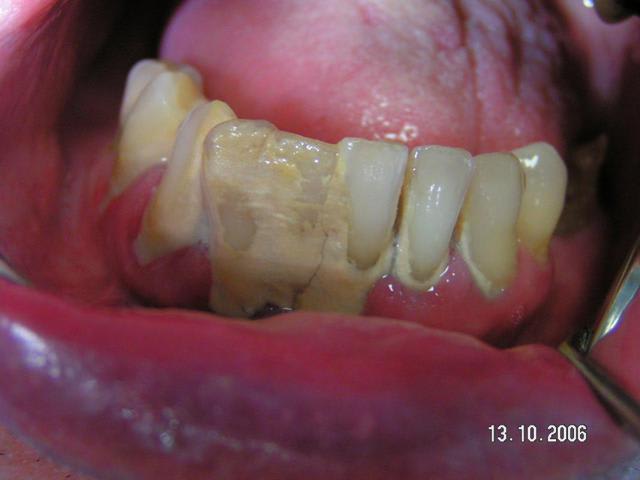

> Nouveau produit : l'enregistrement de la RIM avec le tartre!!

-- la je crois que l'on a le gagnant! du lourd , du très lourd